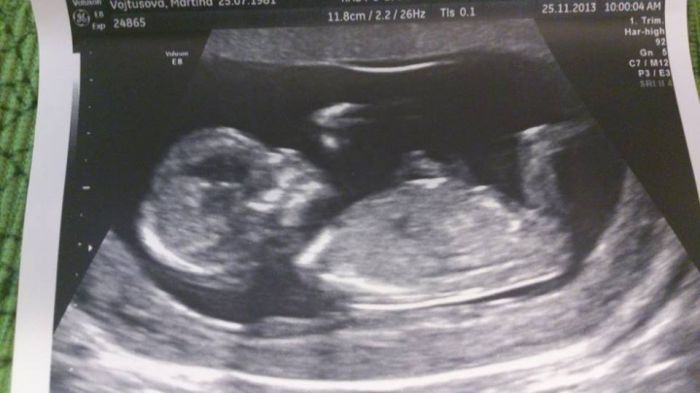

jeste pridavam foto nasi princezny a dneska jsem se rozhodla a bude se jmenovat Ellen.....tata bude mit radost az na kost a moje sestra taky, ti dva totiz jmeno vymysleli

Marti, krásná fotečka!

[397014] Martasku a v kolikatem jsi? Ja jsem 12+4 a nemam z dneska tak hezkou fotku. 3D úplne nepoznatelny a normální docela pěkný, ale třeba nozicky nejdou v podstatě videt.